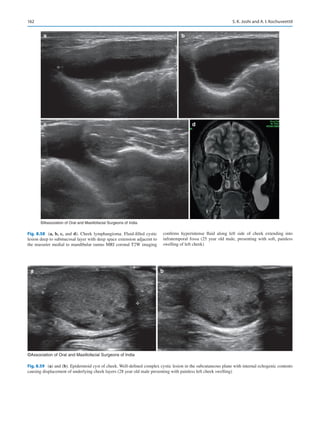

of healthcare tools such as genetic testing is already preva-

lent in many countries. Several patients are aware of which

chemotherapy may be best effective for the management of

1  Oral and Maxillofacial Surgery in India: How Did We Get Here and Where Are We Going?